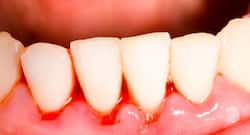

Have Bleeding Gums and Pus? Dentists Warn It Could Be a Sign of Periodontitis

Bleeding gums or pus near your teeth may be early signs of periodontitis. Learn the symptoms, risks, diagnosis steps, and expert advice to protect your teeth and overall oral health.